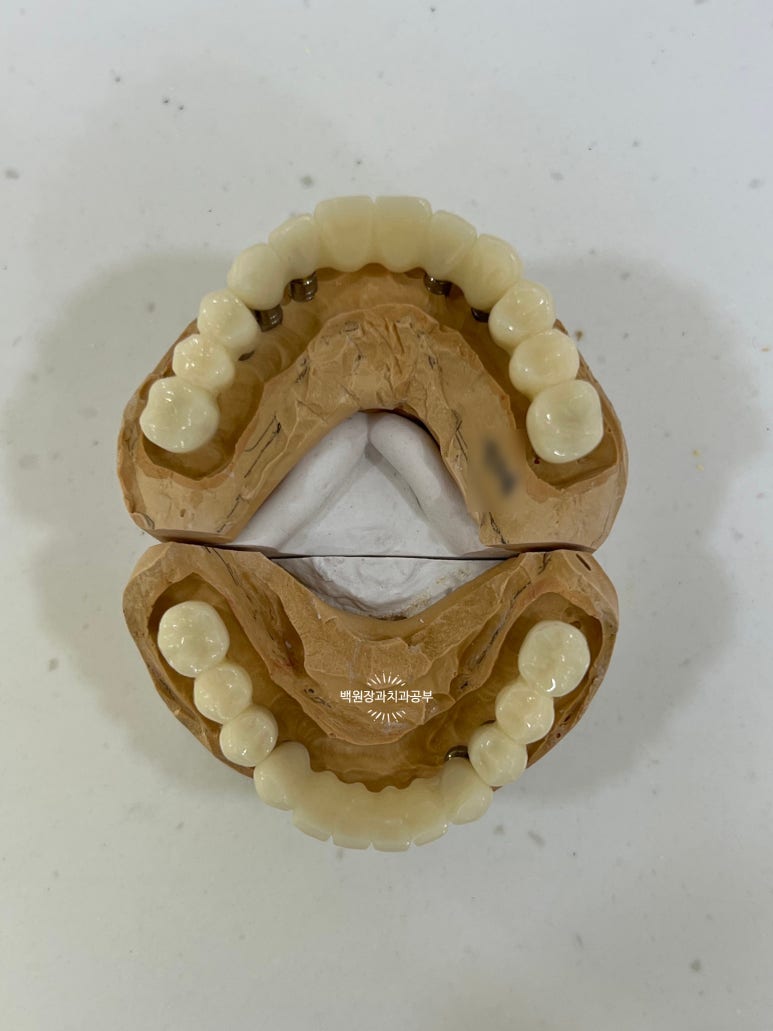

왼쪽이 위턱의 임시치아들이고, 오른쪽이 아래턱의 임시치아들입니다.

이 임시치아를 빼보겠습니다. 그럼 맞춤형 지대주가 보이겠죠?

눈치 빠른 분은 아셨을거에요!! 위가 위턱, 아래가 아래턱입니다.

왜냐?! 지대주가 위가 8개, 아래가 6개잖아요~~ 제가 올려드렸던 치과용 파노라마를 확인해보세요!